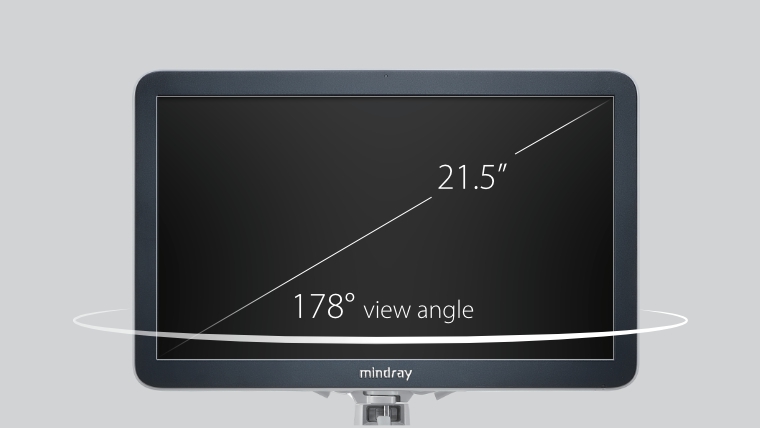

eXceeding Experience

YĂŒksek verimli deneyim